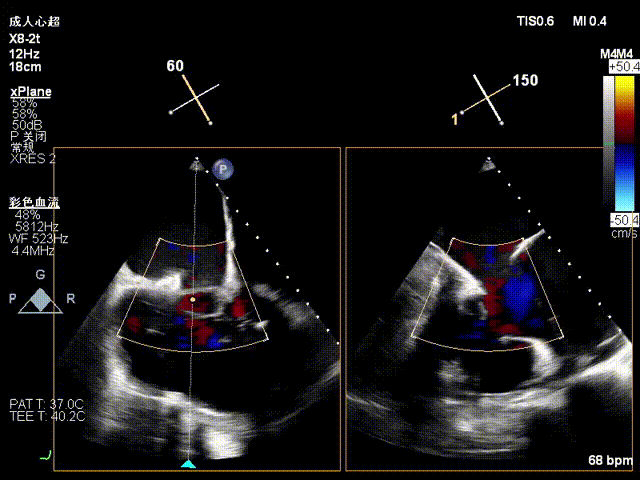

1.TR Reduction: Overall reduction greater than 3+ (decreased from massive 6+ to moderate-to-severe 3+).

Massive 6+

Moderate-to-Severe 3+